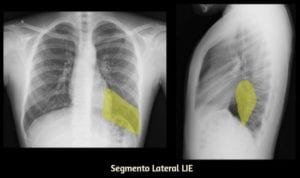

Início/Você Descreve Corretamente a Localização das Imagens Pulmonares nos Exames Radiológicos?/raiox do pulmao 22 raiox do pulmao 22